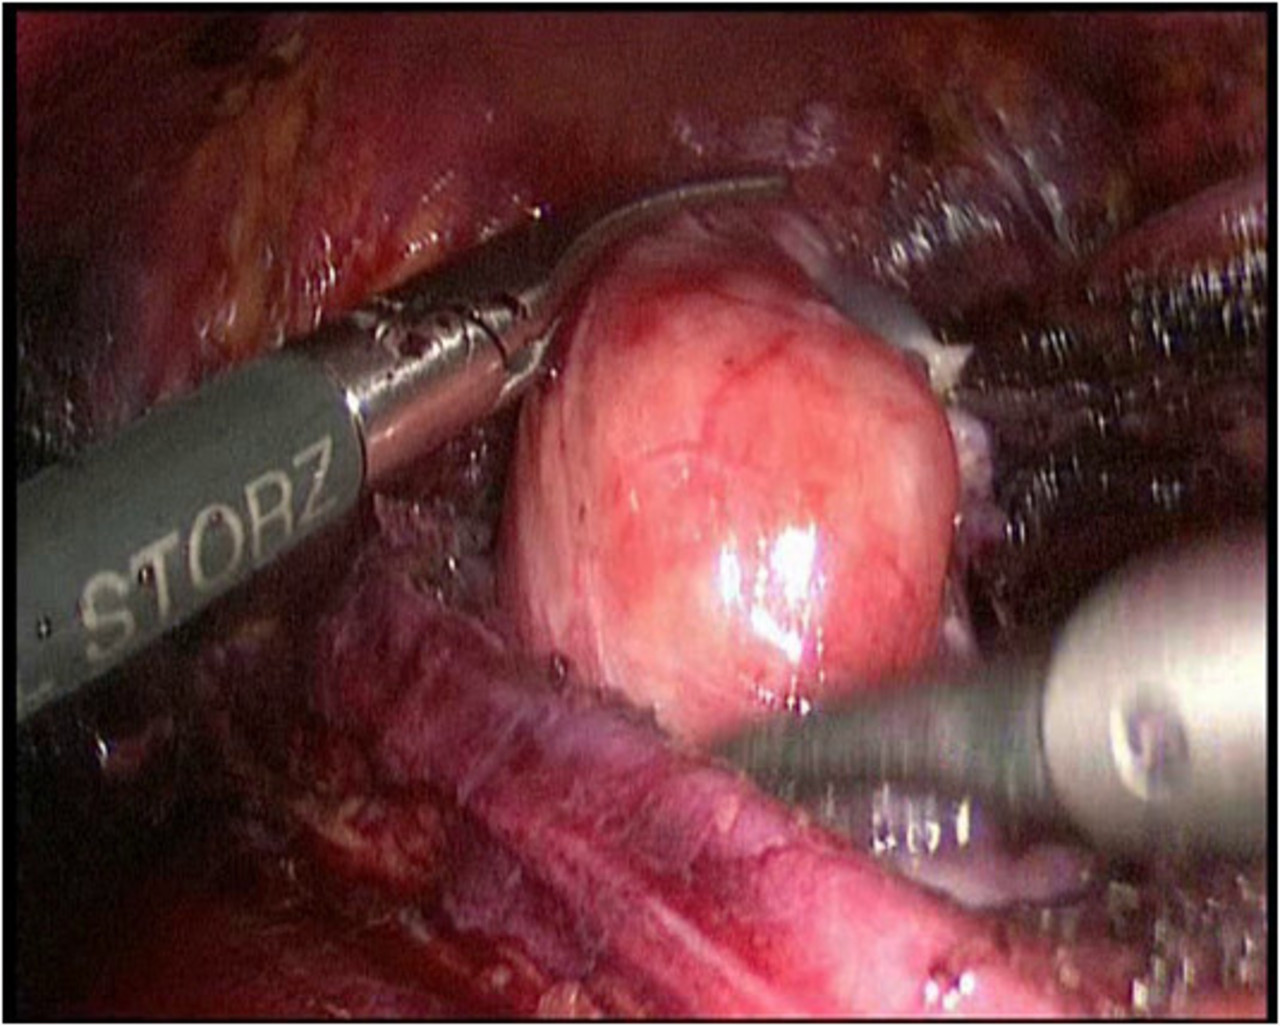

Wir führen neben der konventionellen Schnittoperation seit Jahren auch als eine der wenigen Kliniken in Deutschland die minimal invasive Schilddrüsenresektion nach der „ABBA-Methode“ durch. Welche Operationsmethode im Einzelfalle eingesetzt werden kann hängt von der Schilddrüsenerkrankung und der Größe ab und wird im Vorfeld mit dem Patienten ausführlich abgewogen und besprochen.

Minimal invasive Schilddrüsenoperation (ABBA):

Bei der von uns durchgeführten minimal invasiven Schilddrüsenoperationstechnik handelt es sich um die sog. „ABBA-Technik“ (Axillo-bilateral-breast-approach). Dabei wird die Schilddrüse durch einen ca. 2 cm langen Hautschnitt im Bereich der vorderen Achselhöhle sowie über 2 winzige Schnitte im Bereich der Brust (Randbereich der Brustwarze) operiert. Bei dieser Technik erfolgt die Präparation streng im Unterhautfettgewebe – Nerven, Gefäße oder die Brustdrüse werden dabei nicht tangiert. Ähnlich wie bei minimal invasiven Bauchoperationen wird das Operationsgebiet mit CO2-Gas gefüllt, um ausreichend Raum für die Einführung der feinen Operationsinstrumente zu erreichen. Die Schilddrüse wird dann unter Kamerasicht analog der herkömmlichen Operationstechnik operiert. Die Übersicht bei dieser Operation ist hervorragend; sämtliche Nerven- und Gefäßstrukturen können genau identifiziert werden. Ebenso werden die Stimmbandnerven mittels Neuromonitoring kontrolliert und die Nebenschilddrüsenkörperchen dargestellt und geschont.